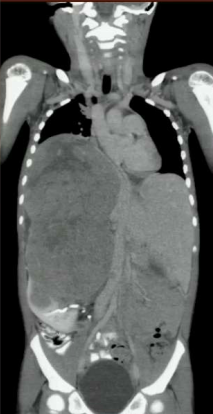

A child presents with fatigue, difficulty breathing and an abdominal mass. What is your diagnosis?

Wilm’s tumor